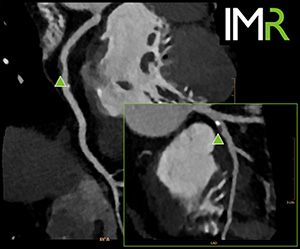

■CT:IMR

RSNA2012にて世界に発表されたIMRが新たにIMR Platinumとしてアップデートされました。Knowledge-Basedアプローチによる逐次近似画像再構成法として,従来の統計学モデルに加え,システムモデルを採用した革新的なテクノロジーにおける新時代の画像をご紹介します。

画像ノイズは最大で90%の低減を可能とし,スライス厚,X線量に依存することなく,Virtual Noise-Free画像を提供します。また低コントラスト領域における描出能は,従来と比較して2.7倍と大幅に向上することで,病変の早期発見や早期治療を支援します。心臓領域においてはMotion Sensitivityモデルを搭載することによって心電図同期への対応を実現します。更にHyperSight IMRと呼ばれる超高速再構成ユニットは,モデルベースの逐次近似画像再構成法として従来課題とされていた画像再構成時間を大幅に短縮し,多くの検査においてわずか3分程度にて演算することを可能としました。